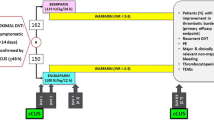

A systematic review of the literature was conducted to compile current evidence for the section on preventative treatments. The Medline (PubMed) database was searched on 5 July 2022, using the search strategy set out in the supplementary materials. The resulting search yielded 235 studies. Criteria used in identifying, screening and excluding studies are outlined in the PRISMA diagram (Fig. 1). The resulting 28 studies were compiled into three sections with anticoagulation in Table 2, elastic compression stockings in Table 3 and catheter-based early thrombus removal in Table 4.

Effective anticoagulation is one of the most effective strategies to prevent PTS, through early thrombus resolution by preventing thrombus propagation, and therefore reducing valve damage and residual vein obstruction, two of the major causes of PTS [54]. However, the duration of anticoagulation to treat DVT is not associated with improved clinical outcome, which was demonstrated in the ExACT randomised controlled trial (RCT) [55]. However, the time in the therapeutic range is critical, with subtherapeutic anticoagulation with vitamin K antagonists (VKAs) shown to increase the risk of PTS in several studies. [3, 41, 56]. This finding raises important questions about the type of anticoagulation used, particularly in the era of direct oral anticoagulants (DOAC), where all but one study shows DOACs to be associated with reduced likelihood of PTS (Table 2), likely in part due to their stable anticoagulation effect. The study that showed no difference [57] was a Danish registry study that relied on the McDougall criteria, based on symptoms and signs in medical records which may not be generalisable to clinical practice. Similarly, studies suggests that LMWH compared to VKAs likely reduce the risk of PTS and improves vein re-canalisation [58,59,60,61], of which the benefit conferred by LMWH may be twofold—more stable anticoagulation effect and possible anti-inflammatory effects [62]. Taken together, the body of knowledge to date highlights that effective anticoagulation is pivotal to reduce the occurrence of PTS.

The evidence for ECS is mixed with several randomised controlled studies (RCT) comparing ECS to no stockings demonstrating around 50% reduction in PTS incidence (see Table 3). However, the largest placebo-stocking controlled trial of 804 patients (‘SOX’ study) [65] failed to show any interventional effect. In this study, PTS developed in 14.2% of the active ECS group vs 12.7% in the placebo group (HR 1.13, 95% CI 0.73–1.76, p = 0.58). However, one reason for the lack of efficacy could be due to the substantially lower compliance rate in this study compared to other RCTs. Barriers to optimal ECS usage may include discomfort, cost and difficulty putting on the stockings. Studies have examined the effect of modifications to the standard ECS regimen to improve compliance and found non-inferior results with reduced compression strength stockings (25 mmHg instead of 35 mmHg) [66], reduced ECS duration to 12 months [67] and an individualised tailored regimen based on Villalta score [68]. These strategies may be adopted in clinical practice to improve compliance with ECS. Nonetheless, the results of the SOX study have proved influential and have resulted in recent VTE guidelines recommending ECS for reduction of symptoms rather than direct prevention of PTS [69, 70].

Table 4 summarises the results of three high-quality randomised controlled trials of CDT/PCDT. The CaVenT study [71] randomised 209 patients with iliofemoral DVT to CDT or standard therapy with anticoagulation alone within 21 days of symptom onset. At two-year follow-up, a minor interventional effect was found (PTS rates 41.1% vs 55.6%, p = 0.047). The final 5-year CaVenT [72] results, however, demonstrated a more marked difference in the intervention group (PTS rates 43% vs 71%, p = 0.001). Major bleeding in CaVenT occurred in 2.7% of the CDT group vs none in the control group. The CAVA study [73] randomised 152 patients to receive ultrasound accelerated catheter-directed thrombolysis (UACDT) or standard therapy in iliofemoral DVT within 21 days of symptom onset. At 1 year, PTS rates were no different for both groups (OR 0.75, 95% CI 0.38–1.50, p = 0.42), although the final follow-up (median 39 months) demonstrated lower PTS rates in the interventional group (46.8% vs 69%, OR 0.40 95%CI 0.19–0.84, p = 0.01) [74]. Major bleeding occurred in 5% of the CDT group vs none in the control group.

The ATTRACT study [75] randomised 692 patients including both iliofemoral and femoropopliteal DVTs, to various PCDT techniques (including AngioJet or Trellis pharmacomechanical thrombectomy) against standard therapy. No differences in PTS rates were found at 24 months; however, there was a significant but modest reduction in moderate-to-severe PTS as a composite secondary post hoc outcome in the PCDT subgroup with acute iliofemoral DVT (see Table 4). Major bleeding occurred in 1.7% of PCDT vs 0.3% in the control group (RR 6.18, 95%CI 0.78–49.2, p = 0.049). Several potential causes for the weak effect sizes have been identified in post hoc analyses. PCDT may not be effective for femoropopliteal DVTs (43% of study patients) [76] and is less likely to benefit those over the age of 65 [75]. In addition, PCDT did not significantly reduce incidence of valvular reflux, despite reducing residual thrombus volume [77]. The optimal timing of intervention is also unclear, but it is generally accepted that early intervention derives the greatest benefit. Post hoc analysis of ATTRACT found that intervention within 4–8 days from symptom onset was associated with the greatest benefits in QOL and Villalta scores. Interestingly, no significant improvement was seen in those who received intervention at < 4 or > 8 days [78]. Long-term data from ATTRACT have not been released, but if made available, they may provide additional insights.